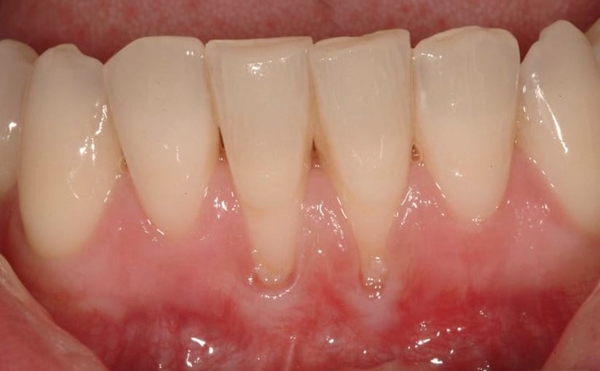

"계속해서 내려 앉는 잇몸, 방치하면 치아를 잃을 수도 있습니다!"

구강 건강이 일상생활에 얼마나 큰 영향을 미치는지 알고 계신가요? 잇몸 건강은 치아만큼 중요합니다. 잇몸이 내려 앉는 현상은 많은 사람에게 흔히 발생하며, 이를 방치하면 치아의 지지력이 감소하고 심각한 경우 치아 상실로 이어질 수 있습니다. 그래서 오늘은 잇몸이 내려 앉을 때의 원인과 문제를 이해하고, 이를 해결하기 위한 잇몸이 내려 앉을 때 잇몸 복원치료의 필요성에 대해 논의해보도록 하겠습니다.

구강 건강 전문가들은 잇몸이 내려 앉는 원인으로 여러 가지를 지목하고 있습니다. 치주염은 잇몸 퇴축의 주요 원인 중 하나로, 치아를 지지하는 조직의 염증으로 인해 발생합니다. 또한, 부적절한 구강 위생 관리, 유전적 요인, 흡연, 호르몬 변화 등이 잇몸 퇴축을 유발할 수 있는 주요 요인으로 꼽히고 있습니다.

잇몸이 내려 앉으면 치아 뿌리가 노출되어 미관상 좋지 않은 모습을 초래할 수 있습니다. 잇몸 복원치료는 잇몸을 재건하여 자연스럽고 건강한 미소를 되찾게 해줍니다. 이는 환자의 자신감을 높이고 사회적, 심리적 복지를 향상시킵니다. 아름다운 미소는 사람들 간의 교류에서 중요한 요소로 작용하며, 외모에 대한 자신감이 사회적 상호작용에도 긍정적인 영향을 미칩니다.